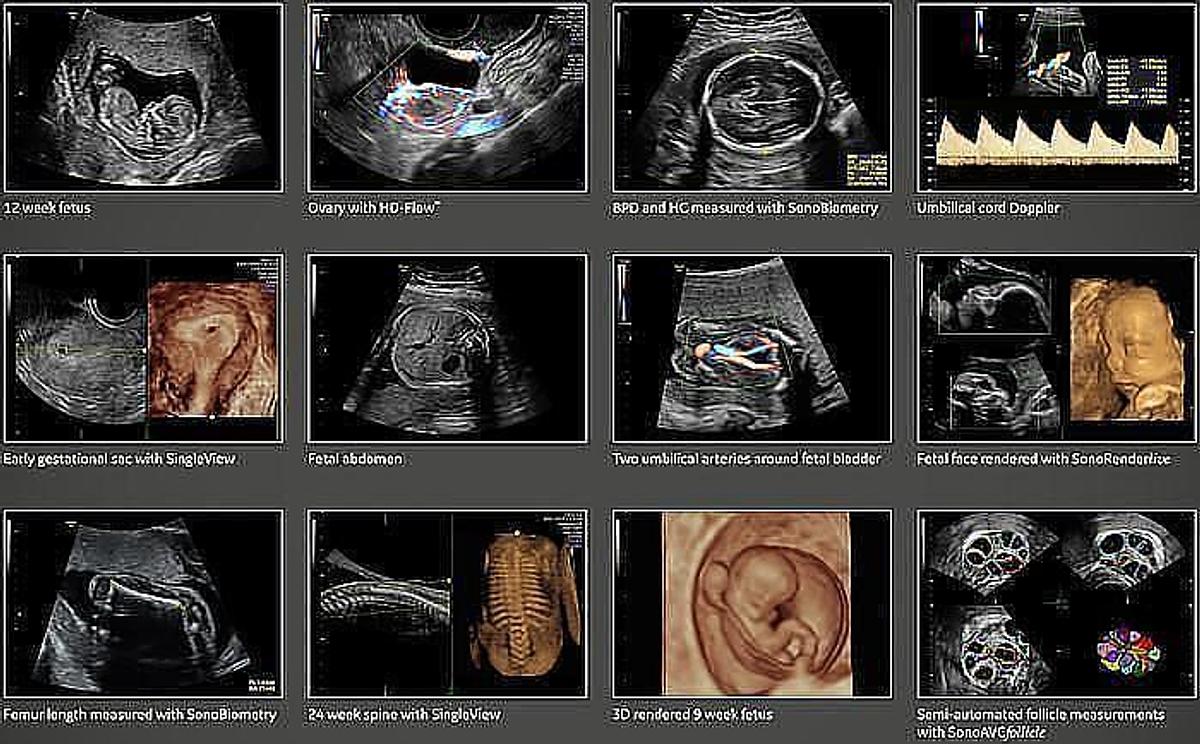

- Calidad de imagen superior: La tecnología de reducción de ruido mejora aún más la claridad de la imagen 2D.

- Versatilidad: El sistema es adecuado para una amplia gama de aplicaciones, incluyendo imágenes abdominales, vasculares, OB/GYN y más.

- Utiliza tecnologías de Sono-automatización para reducir la complejidad y aumentar la consistencia de los exámenes.

- SonoRenderlive automatiza la colocación de la línea de renderizado en imágenes 3D/4D para una fácil adquisición de imágenes.

- SonoBiometry ofrece mediciones de biometría semiautomatizadas (BPD, HC, AC, FL y HL) para reducir la cantidad de pulsaciones de teclas.

- Velocidad y versatilidad: El Voluson P8 permite a los médicos adquirir imágenes detalladas más rápido que nunca. Su velocidad, consistencia y versatilidad en la obtención de imágenes permiten exámenes eficientes y de alta calidad en una variedad de aplicaciones clínicas, incluso en casos técnicamente desafiantes como pacientes con un alto IMC.

- Modos de flujo avanzado: Incluye Color Flow, Power Doppler Imaging y Microvascular Imaging (MVI) para una visualización detallada del flujo sanguíneo.

| Aplicaciones disponibles: | Abdominal, Obstétrico, Ginecológico, Mama, Pequeñas partes. |

| Modos de operación: | B-Modo, M-Modo, Modo Color Flow y B-Flow. |

| Modos de Volumen (opcionales): | 3D/4D |